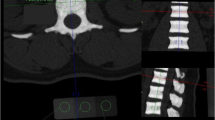

In vivo molecular imaging showed higher axial OsteoSense 750 signals in 8-week-old ank/ankmice

Figure 3 shows the representative biodistribution of OsteoSense 750 signals of wild-type versus ank/ank mice (12 weeks; Figure 3A and 3B). Areas (in red) were marked for calculation of fluorescence signals (circled). As expected, paw joints of ank/ank mice from all three groups showed significantly higher fluorescence signals (expressed in mean photon counts with 95% confidence intervals) than did those of normal (+/+) littermates. The paw signals in ank/ank mice were 148 (112.1 to 184.8), 169.5 (111.3 to 227.8), and 87 (64.9 to 109) at 8, 12, and 18 weeks, respectively, compared with 84.4 (67.5 to 101.2), 64.9 (46.1 to 83.6), and 58.9 (31.6 to 86.2) at the corresponding age groups of wild-type littermates (Figure 4A). Interestingly, as early as 8 weeks of age, mean fluorescence signals from the lower spines of ank/ank mice were significantly higher than those from the wild-type (+/+) littermates of the same age group. At 8, 12, and 18 weeks, the spinal signals were 319.3 (274.9 to 363.7), 253.7 (177.1 to 330.3), and 271.1 (169.0 to 373.1), respectively, in ank/ank versus 200.2 (141.9 to 258.4), 134.7 (93.2 to 176.1), and 130.4 (111.7 to 149.1), respectively, in wild-type mice (Figure 4B). Comparisons of paw and spinal signals between wild-type and ank/ank mice in all three age groups showed significant differences (P < 0.05 at each age group; Figure 4A and 4B and Table 1).

In vivo imaging of wild-type versus ank/ank mice after injection of OsteoSense 750 probes. (A, B) Scans of 12-week-old wild-type versus ank/ank mice to identify fluorescent signals. For quantification of signals, selected areas for distal paws and spine are circled in yellow and white, respectively (C, D).